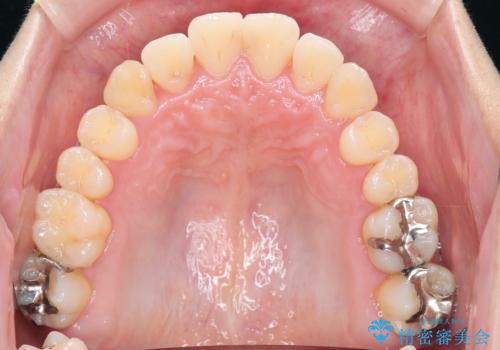

ねじれ・がたつきのある前歯を改善

見た目の改善だけでなく、噛みやすくなったことにも満足いただくことができました。